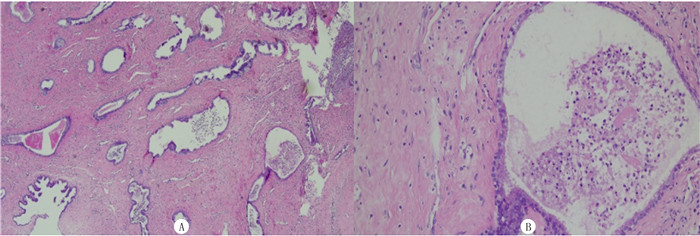

| A:术后病理HE染色,40倍;B:术后病理HE染色,200倍。 图 1 子宫内膜息肉术后病理检查(2021-01-08) |